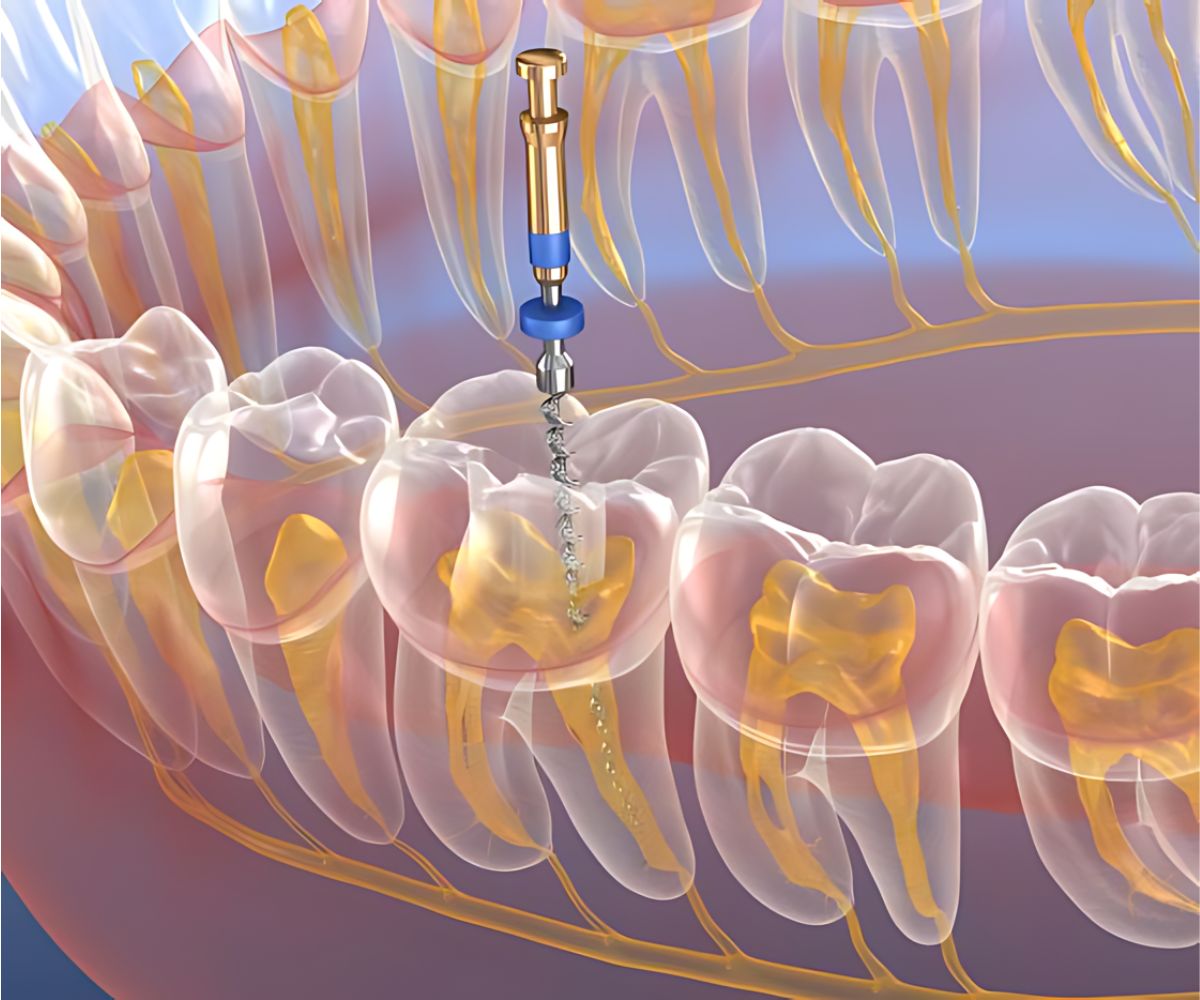

Root canal treatment is a vital procedure designed to save a severely infected or damaged tooth instead of extracting it. When the pulp inside your tooth (containing nerves and blood vessels) becomes inflamed or infected, it can cause severe pain and discomfort. During a root canal, the infected pulp is carefully removed, the inside of the tooth is cleaned and disinfected, and then filled and sealed. This precise root canal procedure allows you to retain your natural tooth, preventing further complications. At True Dental Co, we focus on precise, pain-free root canal treatment to ensure your comfort and preserve your tooth.